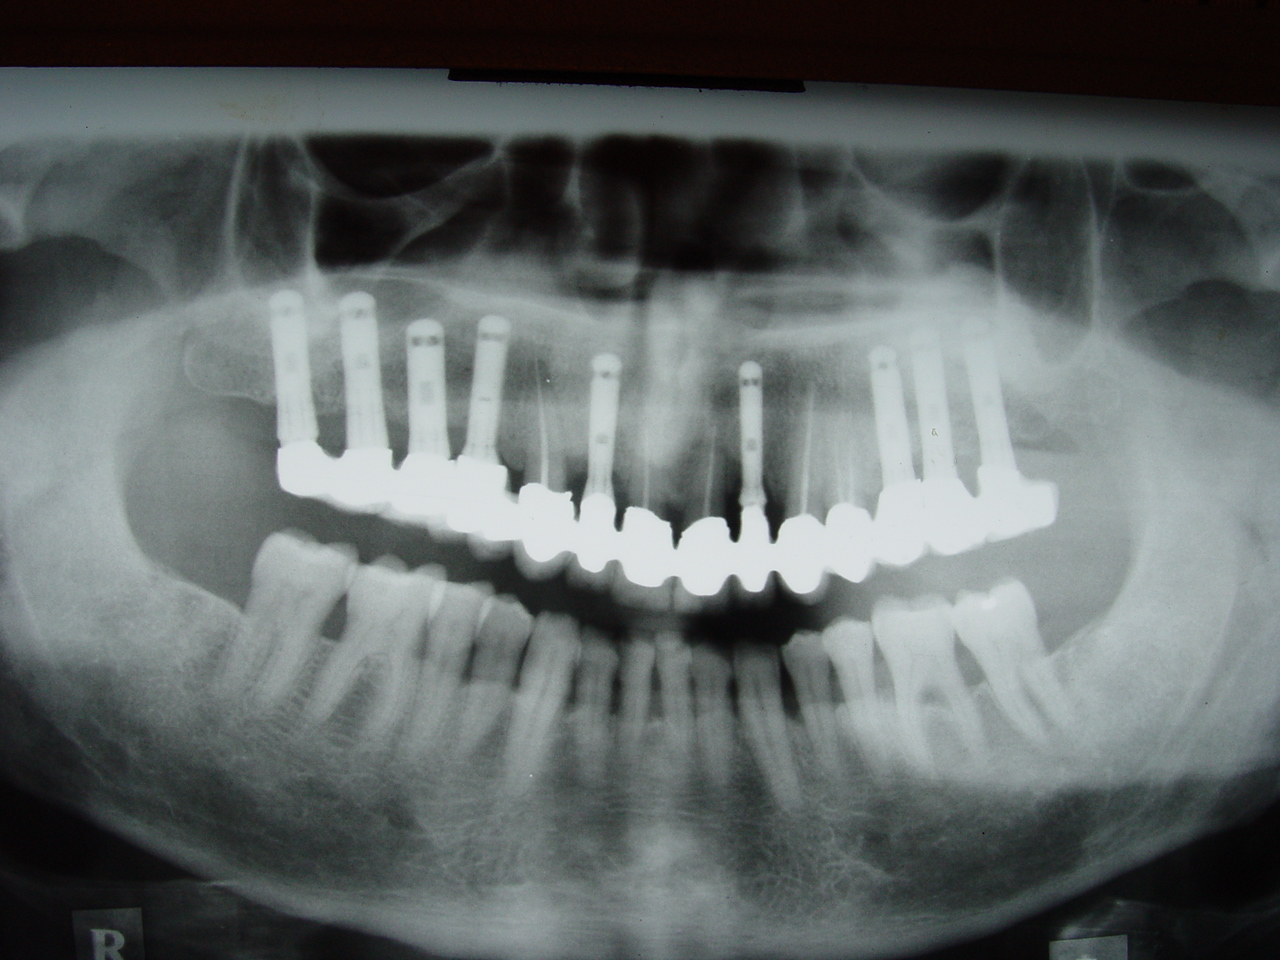

לאחר כ-3 עד 6 חודשים תשובו עם צלום פנורמי להמשך טיפול הכולל את חשיפת השתלים שזוהי פעולה כירורגית פשוטה ולא כואבת, ולאחר מכן יחל תהליך שיקום הפה כמתוכנן. (כתרים גשרים וכו').עם סיום השיקום תזומנו אחת לארבעה חודשים לטיפול מונע אצל השיננית, ולאחר כשנה תזומנו עם צילום פנורמי לביקורת אצל הרופא.

- צילום פנורמי עם שתלים